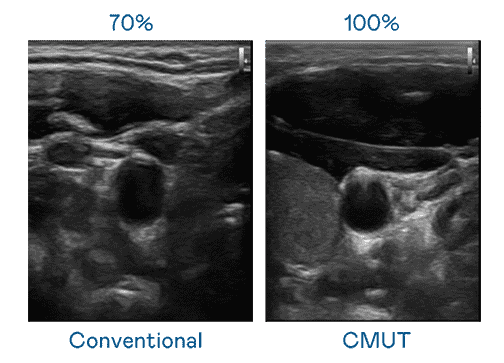

CMUT 技术是一种用电容式微机电元件来产生超音波讯号的技术。。。与传统 PZT 压电式技术相比,,,CMUT 频宽增加 30%,,,,更宽频的超音波讯号让影像解析度大幅提升,,,是实现高影像品质医疗超音波扫描、、、促进精准医疗发展的关键技术。。

大频宽带来超清晰影像

超音波影像的解析度高低,,首先取决于探头能发出的讯号频宽。。。OBPay CMUT 可提供高清晰的超音波讯号,,,,提供高频宽、、、、高灵敏度、、、影像纹理细节更高的超音波影像,,,协助医护人员缩短影像判读时间及利用精准的医疗影像进行诊断。。